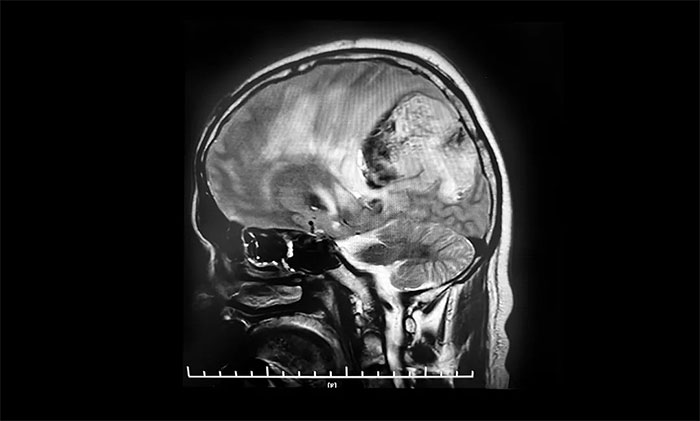

頭顱MRI平掃+增強+DWI+MRA提示,左側(cè)頂枕葉巨大腫瘤伴局部瘤卒中,幕上腦室系統(tǒng)、腦干受壓變形,中線結(jié)構(gòu)右移19mm,大腦鐮下疝形成。李士其教授等專家團隊會診指出,患者腦內(nèi)巨大占位,性質(zhì)不明,并且患者已經(jīng)發(fā)生腦疝昏迷,生命危在旦夕,應(yīng)盡快進行手術(shù)治療,挽救患者生命,同時明確病理診斷。

▲ 左側(cè)頂枕葉巨大腫瘤伴局部瘤卒中